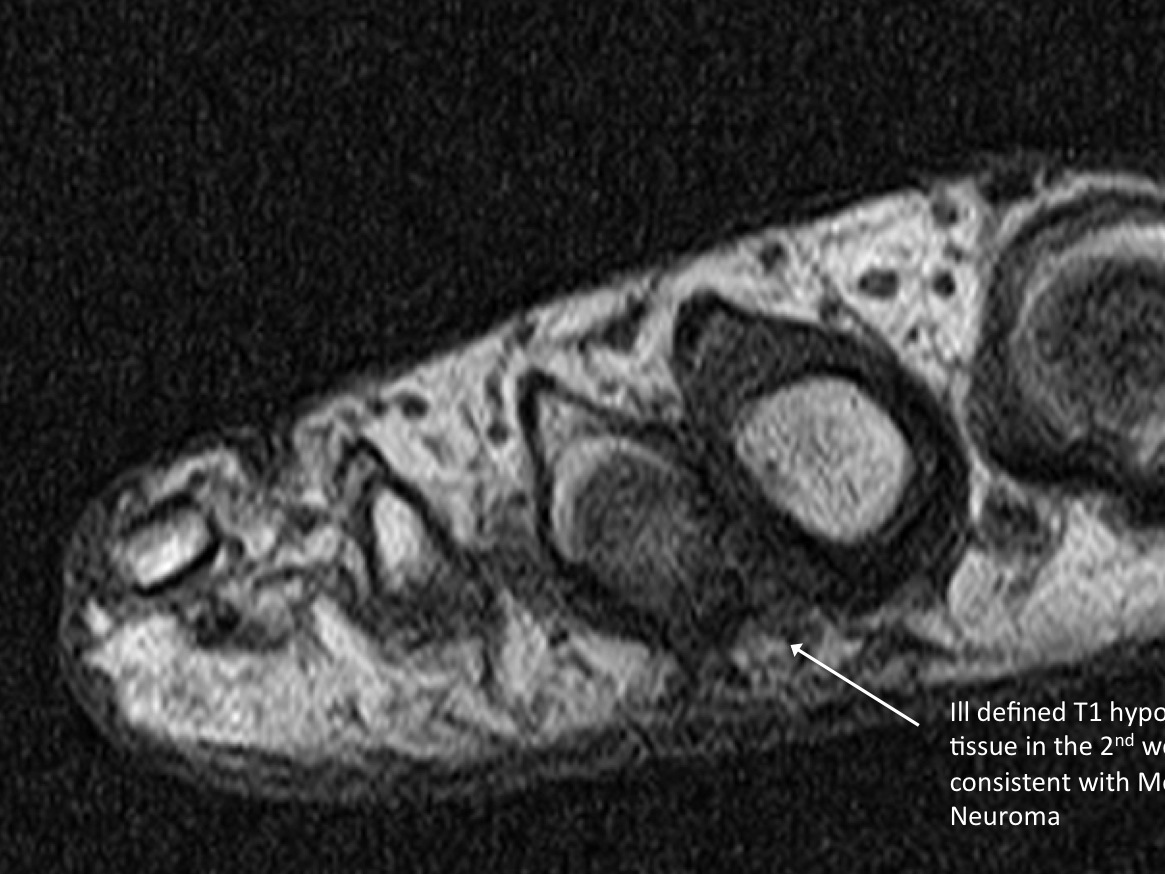

• probe: 9Mhz linear probe

3. Pre-procedure scanning looking from either plantar or dorsal looking for Morton’s neuroma in the webspaces. Place probe in long axis along the distal metatarsals. If well visualized from the dorsal aspect, prefer to place ultrasound probe in that position. Sometimes, it is preferred to have the patient dorsiflex and have the probe plantar, particularly when the patient has subluxations of the MTP joints.